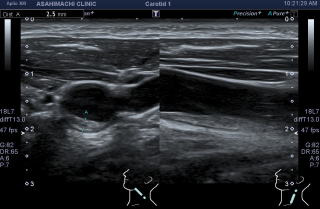

頚動脈エコーは動脈硬化の検査方法としてとても信頼できる検査法です。つらくなく簡単に血管の中をみることができます。

血管の中にコレステロールのかたまり(プラーク)がたくさんついています。

これも白い部分が血管の中についたコレステロールのかたまり(プラーク)です。